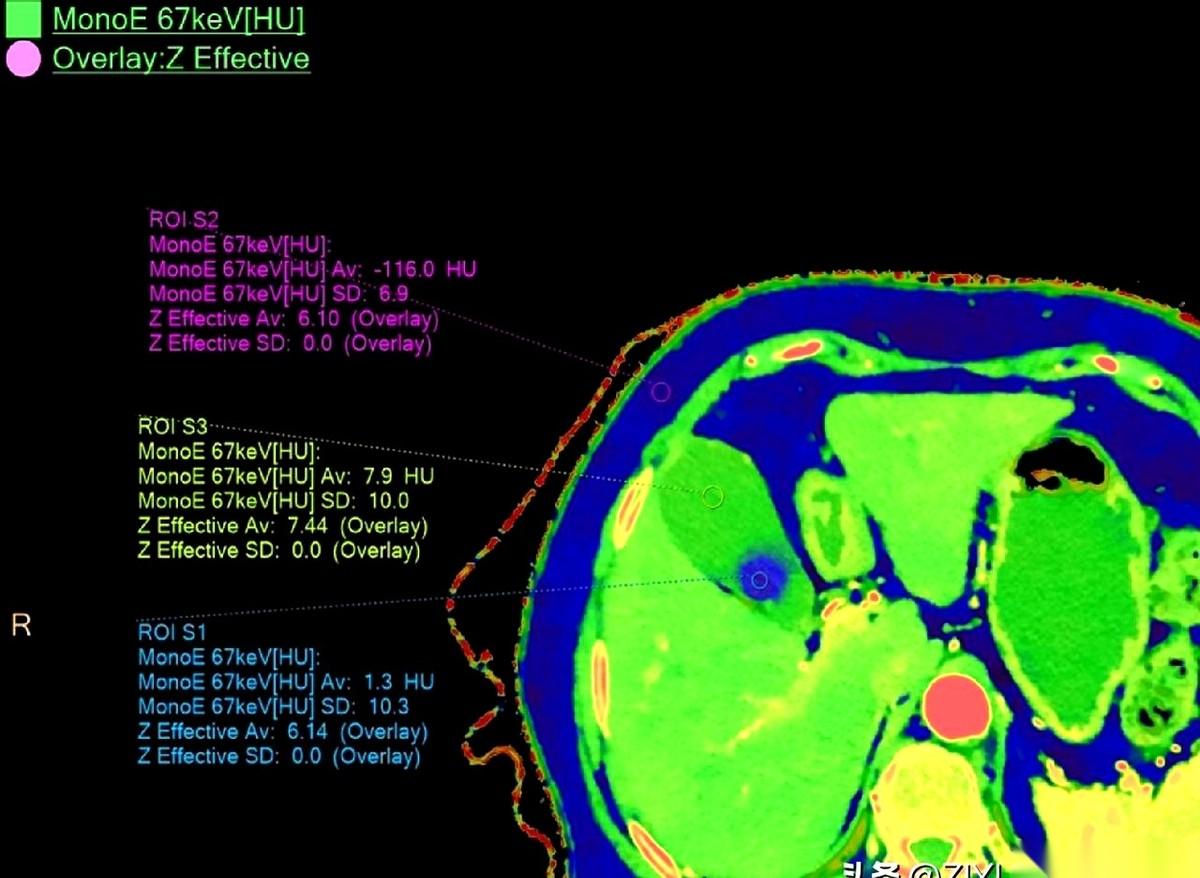

我跟你讲个事儿,绝了。 一个阿姨,肚子疼了20天,跑去做CT,报告白纸黑字写着:胆囊没毛病。 可她就是疼啊!转头又去做了个B超,好家伙,B超上清清楚楚,一堆石头。 同一个胆囊,同一个时间,俩机器,两种命。 这找谁说理去? 后来才知道,石头这玩意儿,也分“三好学生”和“隐形刺客”。 阿姨得的那种,叫胆固醇结石。说白了,就是一肚子“油”结晶了。 这东西密度低,跟胆汁儿差不多。 在普通CT眼里,它俩就是一伙儿的,跟透明的冰块扔进了白开水里一样,根本看不出来。CT报告当然写“没事”。 但B超不一样,它靠的是耳朵,是声波。 石头和液体,在它听来,动静完全不同。一下就给揪出来了。 所以啊,有时候真不是机器骗你。 是你身体里那个“对手”太狡猾。 这事儿给我最大的感触就是,别太迷信一张报告。 尤其是当你的身体还在持续发出警报的时候。 你的疼,你的难受,才是最真实的报告。 机器是死的,人是活的。多问一句,换个法子查,可能就是天壤之别。 千万,千万要信你自己的身体。 它不会骗你。